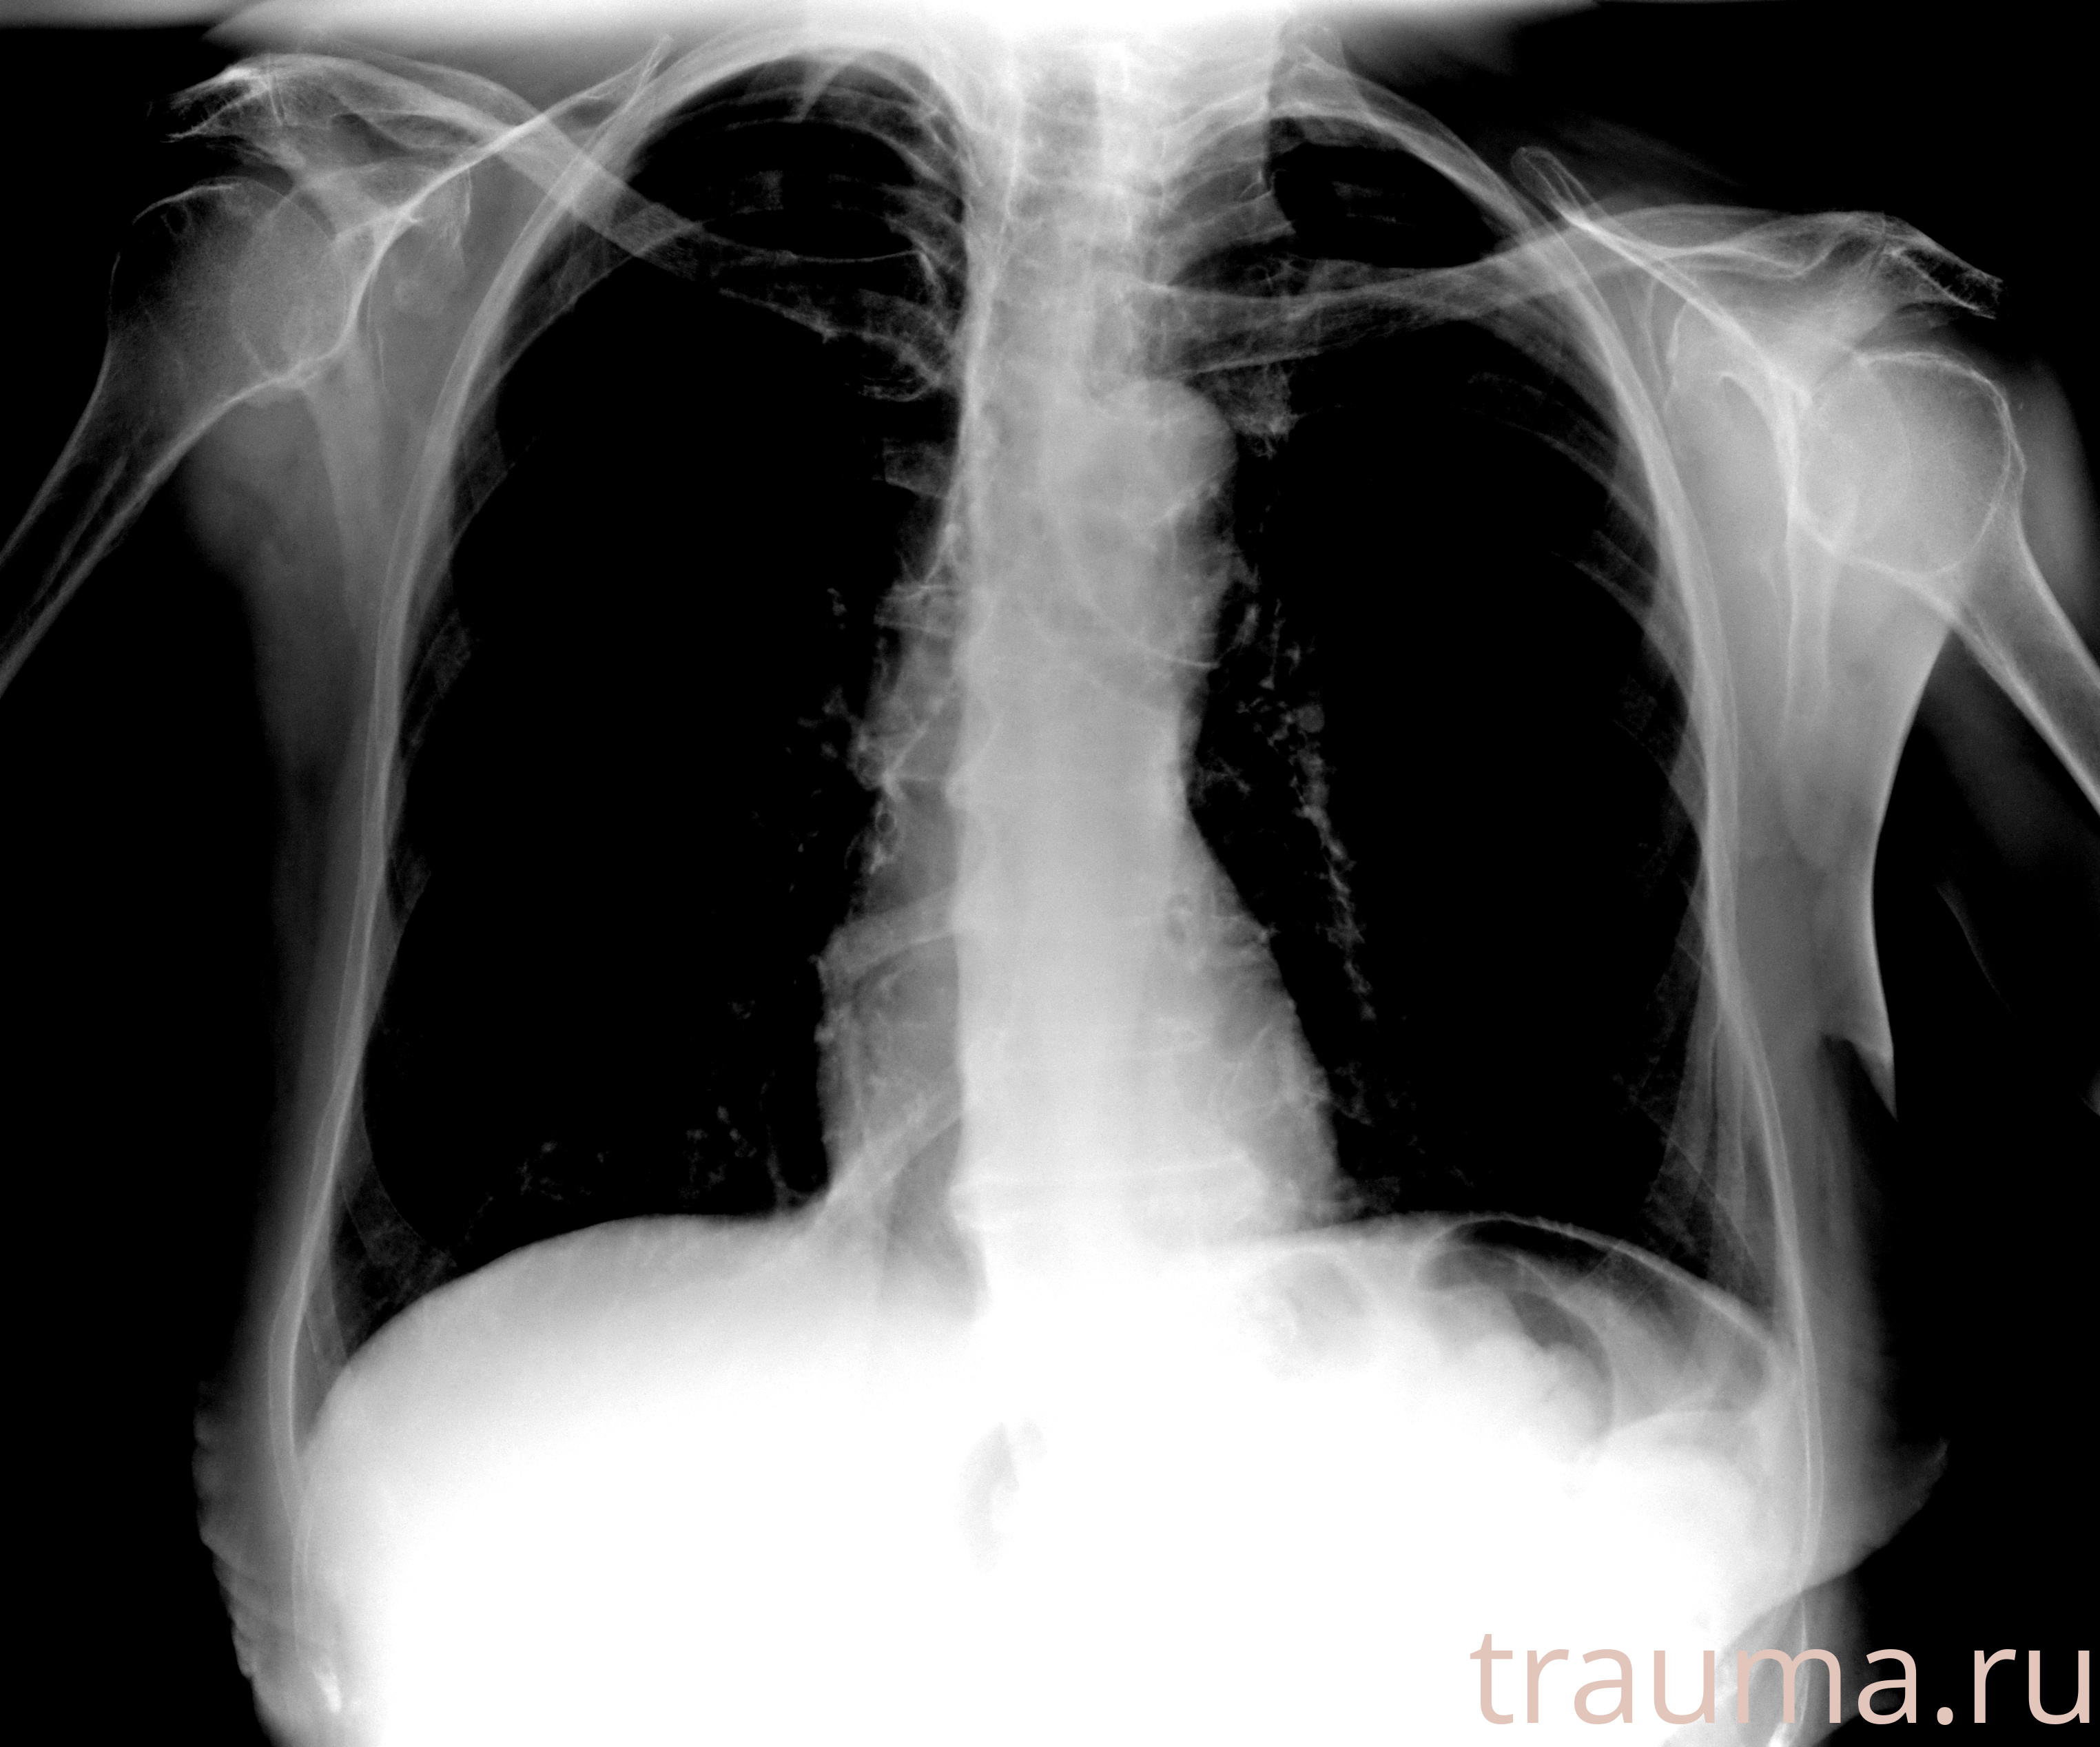

Рентгенограммы

Рентген на дому: по вашему адресу приезжает врач-рентгенолог, травматолог-ортопед с мобильным рентгеновским аппаратом, проводит диагностику травмы или заболевания, делает необходимые рентгенограммы, дает рекомендации по дальнейшему лечению. Получить качественные снимки в домашних условиях возможно благодаря уникальной методике, разработанной МосРентген Центром для института  Склифосовского